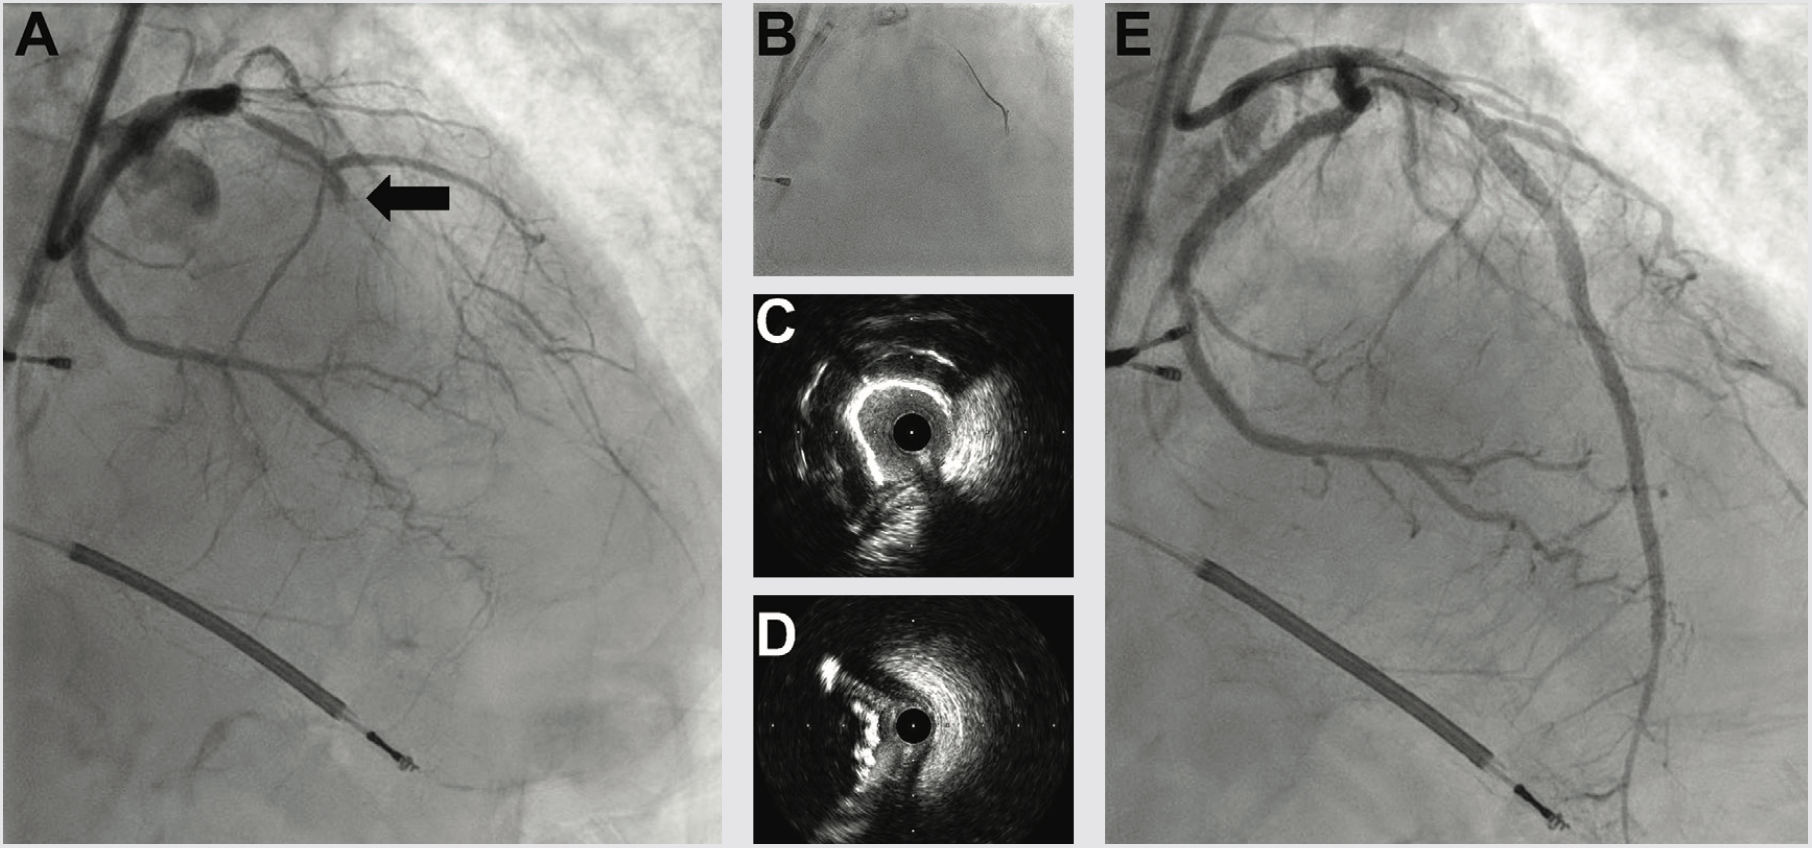

A 73-year-old male with a past medical history of coronary artery disease (CAD) and recent onset congestive heart failure on optimal medical therapy presented with Canadian class 3/4 angina for consideration of revascularization. The patient had a history of peripheral artery disease with a right iliac stent and right common femoral artery endarterectomy with patch repair. He also had a new ischemic cardiomyopathy with a left ventricular ejection fraction (LVEF) of 25%. Complete blood count was within normal limits and the creatinine was 1.2 mg/dL. Diagnostic angiography done 2 months prior demonstrated left-dominant anatomy with severe calcific CAD (Figure 1). The left anterior descending (LAD) artery was a chronic total occlusion (CTO), the obtuse marginal 1 (OM) was a CTO, the distal left circumflex (LCX) to left posterior descending artery (LPDA) system had a 95% stenosis, and the nondominant right coronary artery was a functional CTO (not shown). Positron emission tomography viability study showed global viability and a LVEF of 20%. The patient had poor targets for surgical revascularization and was turned down for coronary bypass grafting, so we offered high-risk percutaneous coronary intervention (PCI).

We next delivered the Impella CP and using single access guide technique (SHiP) through the Impella insertion sheath, placed a 7 French (Fr) left main guide, planning to treat the complex disease in the left circumflex. Diagnostic angiography demonstrated that the distal LCX to LPDA had progressed to a functional CTO. Using an antegrade wire escalation (AWE) strategy, we wired the LPDA with a Pilot 200 wire (Abbott Vascular), redirecting from a subintimal location to the artery true lumen. Predilation balloons would not expand, and intravascular ultrasound (IVUS) showed a severe arc of calcium and nodular calcium in the mid and distal LCX (Figure 3). With the assistance of a deep-seated guide extender, we treated with a 3.0 mm Shockwave balloon to modify the calcium compliance to facilitate optimal stent expansion (Figure 3). After Shockwave treatment, 1-to-1 sized AngioSculpt scoring balloons (Philips) expanded well, and we placed overlapping drug-eluting stents distal to the OM1 CTO into the LPDA. We next tackled the OM1 CTO with an AWE strategy. Using a Mongo wire (Asahi Intecc), we redirected from a subintimal location to the true lumen of the OM1. After 2.0 mm balloon inflation and nitroglycerine administration, the OM1 diameter was small, so we opted to stop at a balloon angioplasty result with non-flow limiting dissection, rather than placing a stent. We finally stented the proximal to mid left circumflex, IVUS optimized the stent expansion, and achieved an excellent IVUS and angiographic result (Figure 3). Having used 180 ccs of contrast to achieve the 2-vessel CTO AWE revascularization, we opted to stage the LAD CTO PCI procedure. We weaned the Impella in-lab, explanted the device, and the patient was discharged 3 days later at baseline renal function.